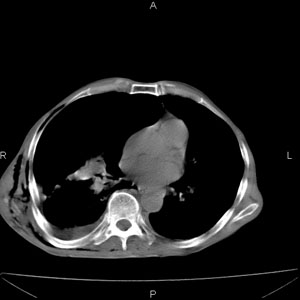

患者男,77岁,于3日前从树上摔下,头部查ct示蛛血,硬膜下出血,上腹部ct未见明显异常,右侧胸腔积液,左侧如常。肺部拍片示右侧肋骨多发骨折住院后今日来查肺部ct,我看到的是1。右侧胸腔血气胸并右肺上叶,中叶压缩性肺不张,2。右肺下叶肺挫伤并多发肋骨骨折,肌内及皮下积气3。左侧少量胸腔积液,我想请教的是3天前左侧胸腔里没有积液今天怎么出现了呢,是什么原因呢?请讨论。